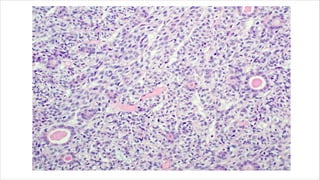

• Confluent nodules composed of uniform, polygonal epithelioid cells

with well developed eosinophilic cytoplasm.

• Nuclei is uniform and bland at low power.

• Infiltrates by lymphocytes can also be present.

• Foci of hemorrhage, necrosis or hemosiderin deposits are common.

• At the periphery, epithelioid cells merge with spindle cells.